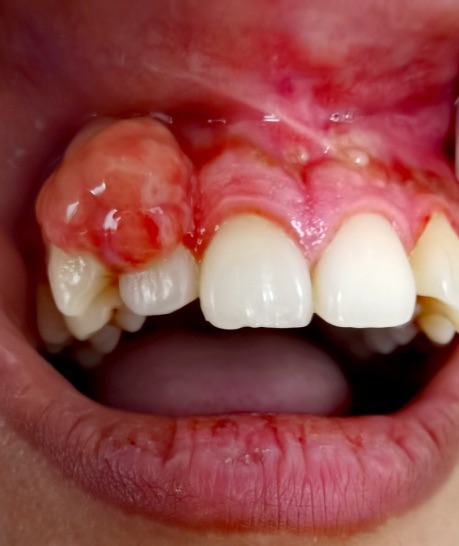

(作者供图 牙龈瘤)

“医生,我现在怀孕5个月,每天刷牙出血怎么办?” “医生,我牙疼的睡不着,可我怀孕了,能做治疗吗?” “医生,我脸肿了2天了,可现在怀孕了不敢吃药怎么办啊?” 临床上,我们经常接到此类患者,这些妊娠期妇女正在被各种口腔疾病困扰,而她们多数是没有做过孕前口腔检查的,那么孕前口腔检查究竟有必要吗? Part1 孕期可能发生哪些口腔疾病? ·牙龈炎和牙周炎 牙龈是女性激素的靶组织,妊娠时血液中的女性激素特别是黄体酮水平增高,使牙龈对局部刺激的反应增强,导致牙龈毛细血管扩张充血,血管通透性增加,炎症细胞和液体渗出增加,加重原有的牙龈炎症。妊娠期龈炎可表现为牙龈的炎症,如红肿、出血等,也可表现为一个或多个牙龈乳头呈瘤样肥大。患者一般在妊娠前即有不同程度的慢性龈炎,从妊娠2~3个月后出现明显症状,到8个月时达到高峰,分娩后约2个月时,牙龈可减轻至妊娠前水平。需要注意的是,并不是所有人都会得妊娠期龈炎,牙菌斑是妊娠期龈炎的直接病因,妊娠期妇女若不注意维护口腔卫生,致使牙菌斑、牙结石在龈缘附近堆积,才易引发牙龈炎症,更有甚者,会出现牙周骨组织破坏,牙根暴露,牙齿松动,发展为牙周炎。有研究报道患有严重牙周病的孕妇,产生早产和低体重儿的危险性较健康人增加了7倍,所以孕前牙周检查至关重要。